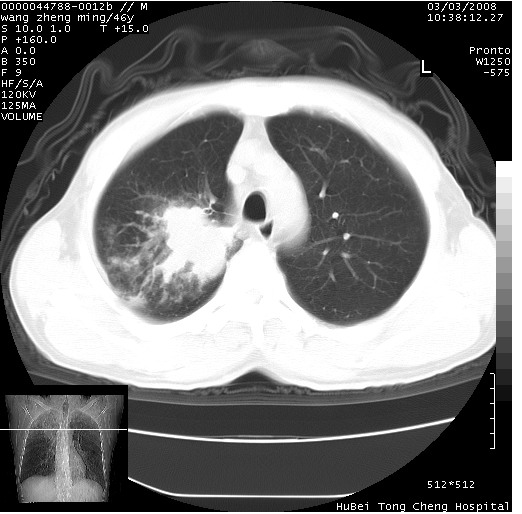

以下是引用卜一在2008-3-22 1:37:00的发言:[br]右肺实质性肿块,边缘不整,明显见毛刺征 分叶征及胸膜凹陷征,右上叶支气管明显变窄,远端散在的片状 斑片状实变影。另:左肺门较大肿块,支气管受累 变窄,远侧见阻塞性肺炎。纵隔内见肿大淋巴结。多考虑:右肺周围性肺癌伴左肺门 纵隔淋巴结转移!